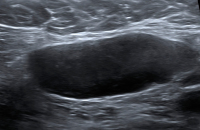

Ultraschall-Lymphknoten

Abbildung 2: Fehlender Hilus. Dieser Lymphknoten weist keinen Hilus auf, alle anderen Kriterien sind jedoch erfüllt. Tumorzellen destruieren die reguläre Architektur des Lymphknotens und führen so zu einer Obliteration der Hilusstruktur. „Diffuse large B-cell lymphoma“ (DLBCL).